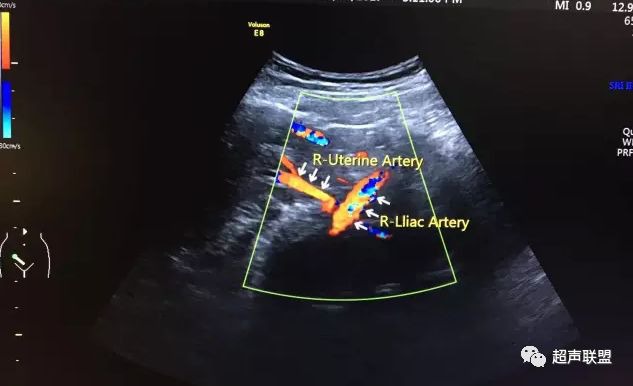

图2 脐动脉舒张期血流消失或反向